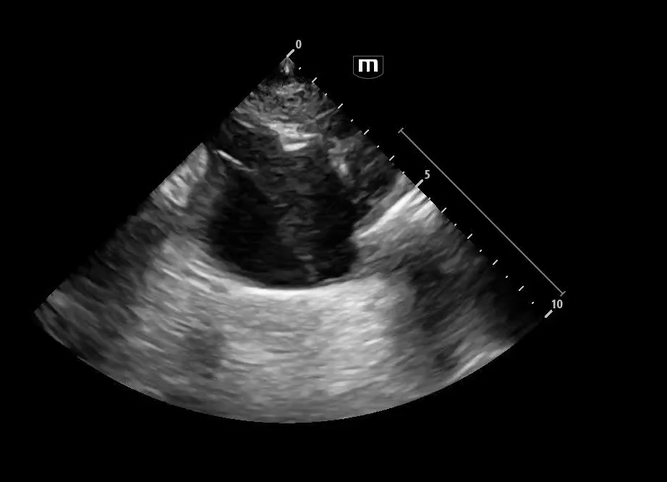

Image 1 & 2: Parasternal long axis

Interpretation: Parasternal long-axis view demonstrating marked dilation of the aortic root, measuring approximately 5.1 cm, concerning for proximal aortic pathology. Preserved EF and no effusions noted.

Teaching point:

• Normal aortic root diameter: < 3.7–4.0 cm

• A diameter >4 cm should raise concern for aneurysm or dissection